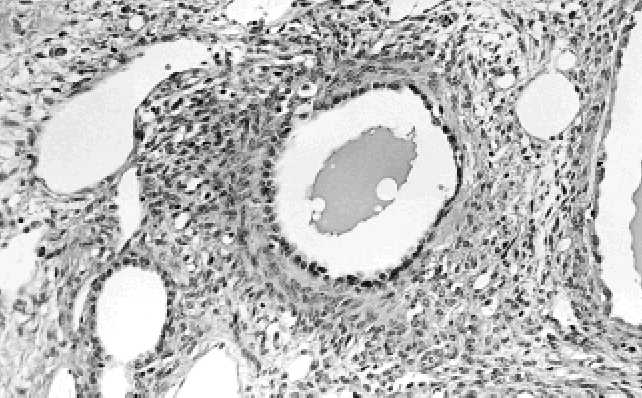

v cystickém nefromu nenachází. Cystický nefrom dětského věku bývá zpravidla bu- něčnější než cystické nefromy v dospělosti. U cystických nefromů v dospělém věku jsou někdy cysty vystlané atypickým světlobuněčným epitelem(227). Vzácně byl po- psán i vznik konvenčního světlobuněčného karcinomu v cystickém nefromu dospě- lého věku(227). V  8 publikovaných případech byla popsána malignizace cystického nefromu do nejrůznějších sarkomů. Jednalo se o nediferencovaný embryonální vře- tenobuněčný sarkom (6 případů), nízce maligní leiomyosarkom (1 případ) a  pleo- morfní vysoce maligní sarkom (1 případ)(23,300). Imunohistochemické  vyšetření.  Stroma  cystického  nefromu  reaguje  pozitivně s protilátkami proti kolagenu IV. typu, hladce svalovému aktinu a desminu. Ostatní imunohistochemické reakce nemají diagnostický význam. Elektronmikroskopické vyšetření. Epitelová v stelka cystického nefromu je vyba- vena krátkými mikrovily(92). Tang a spol. usoudili, že se tento epitel ultrastrukturálně podobá epitelu sběrných kanálků(464). Cytogenetická vyšetření. Cytogenetický profil cystického nefromu je velmi málo znám. Charles a spol. zastihli ztrátu heterozygotnosti u 6 případů cystického nefro- mu/cystického  částečně  diferencovaného  nefroblastomu  na  11p13  chromozómu, u  6 případů na 11p15 chromozómu a  u  2 případů cystického nefromu/cystického částečně diferencovaného nefroblastomu se ztráta heterogenity nacházela na obou místech chromozómů(77). Diferenciální diagnostika. Nejdůležitější je odlišit cystický nefrom od cystického, částečně diferencovaného nefroblastomu. Joshi a Beckwith odlišili tyto dvě jednotky nálezem nezralých nefroblastomových struktur jako například příčně pruhované sva- loviny a  chrupavky, které se nacházejí podle těchto autorů pouze v  částečně dife- rencovaném nefroblastomu(224). S  tímto názorem nesouhlasil Kajani a  spol., protože považovali cystický nefrom a cystický, částečně diferencovaný nefroblastom za dvě různá spektra stejného nádorového procesu, která v sebe přecházejí(227). Tato námit- ka je zcela validní u dětí, avšak neplatná u cystických nefromů dospělého věku, pro- tože  cystický,  částečně  diferencovaný  nefroblastom  se  v   dospělosti  nenachází. Nejpravděpodobnějším vysvětlením bude zřejmě to, že cystický nefrom má dvě růz- né formy. Jednak cystický nefrom dětského věku, který se nachází přibližně stejně často u  chlapců i  u  dívek s  mírnou převahou u  chlapců a  kde je součástí spektra Wilmsova tumoru společně s cystickým, částečně diferencovaným nefroblastomem. Ve shodě s  touto hypotézou je občasný nález intralobárních nefrogenních zbytků u všech těchto tumorů(128). Druhou formou je cystický nefrom dospělého věku, který se na rozdíl od juvenilní formy nachází 8krát častěji u žen. Tento cystický nefrom do- spělého věku bude nejspíše patřit do skupiny nádorů, které byly v  minulosti četný- mi autory publikovány pod nejrůznějšími názvy a které jsme shrnuli v kapitole C.5. pod názvem "smíšené benigní epiteliální a stromální nádory ledvin". Tato forma cys- tického nefromu nemá žádný vztah k  Wilmsově tumoru nebo k  nefrogenním zbyt- kům. Eble a Bonsib navrhují, aby juvenilní forma se vůbec cystickým nefromem ne- nazývala a aby se za cystický nefrom považovala pouze adultní forma cystického ne- fromu(128). Diferenciální diagnostika rozlišování adultní varianty cystického nefromu a  cystického, částečně diferencovaného nefroblastomu v  běžné praxi téměř nepři- chází v  úvahu, protože až na zcela raritní případy(354)  se cystický, částečně diferen- covaný nefroblastom v dospělosti nevyskytuje.   Dále je důležité odlišit multilokulární cystický renální karcinom od cystického ne- fromu.  I  když  se  makroskopicky  tyto  dva  tumory  mohou  podobat,  mikroskopicky jsou cysty u multilokulárního cystického konvenčního renálního karcinomu lemovány 73 72 Obr. C.4.4. V  četných místech je stroma cystických nefromů často velmi buněčné a  může věrně napodobovat ovariální stroma. Obr. C.4.5. V septech cystických nefromů se často nacházejí miniaturní cystičky a tubuly.